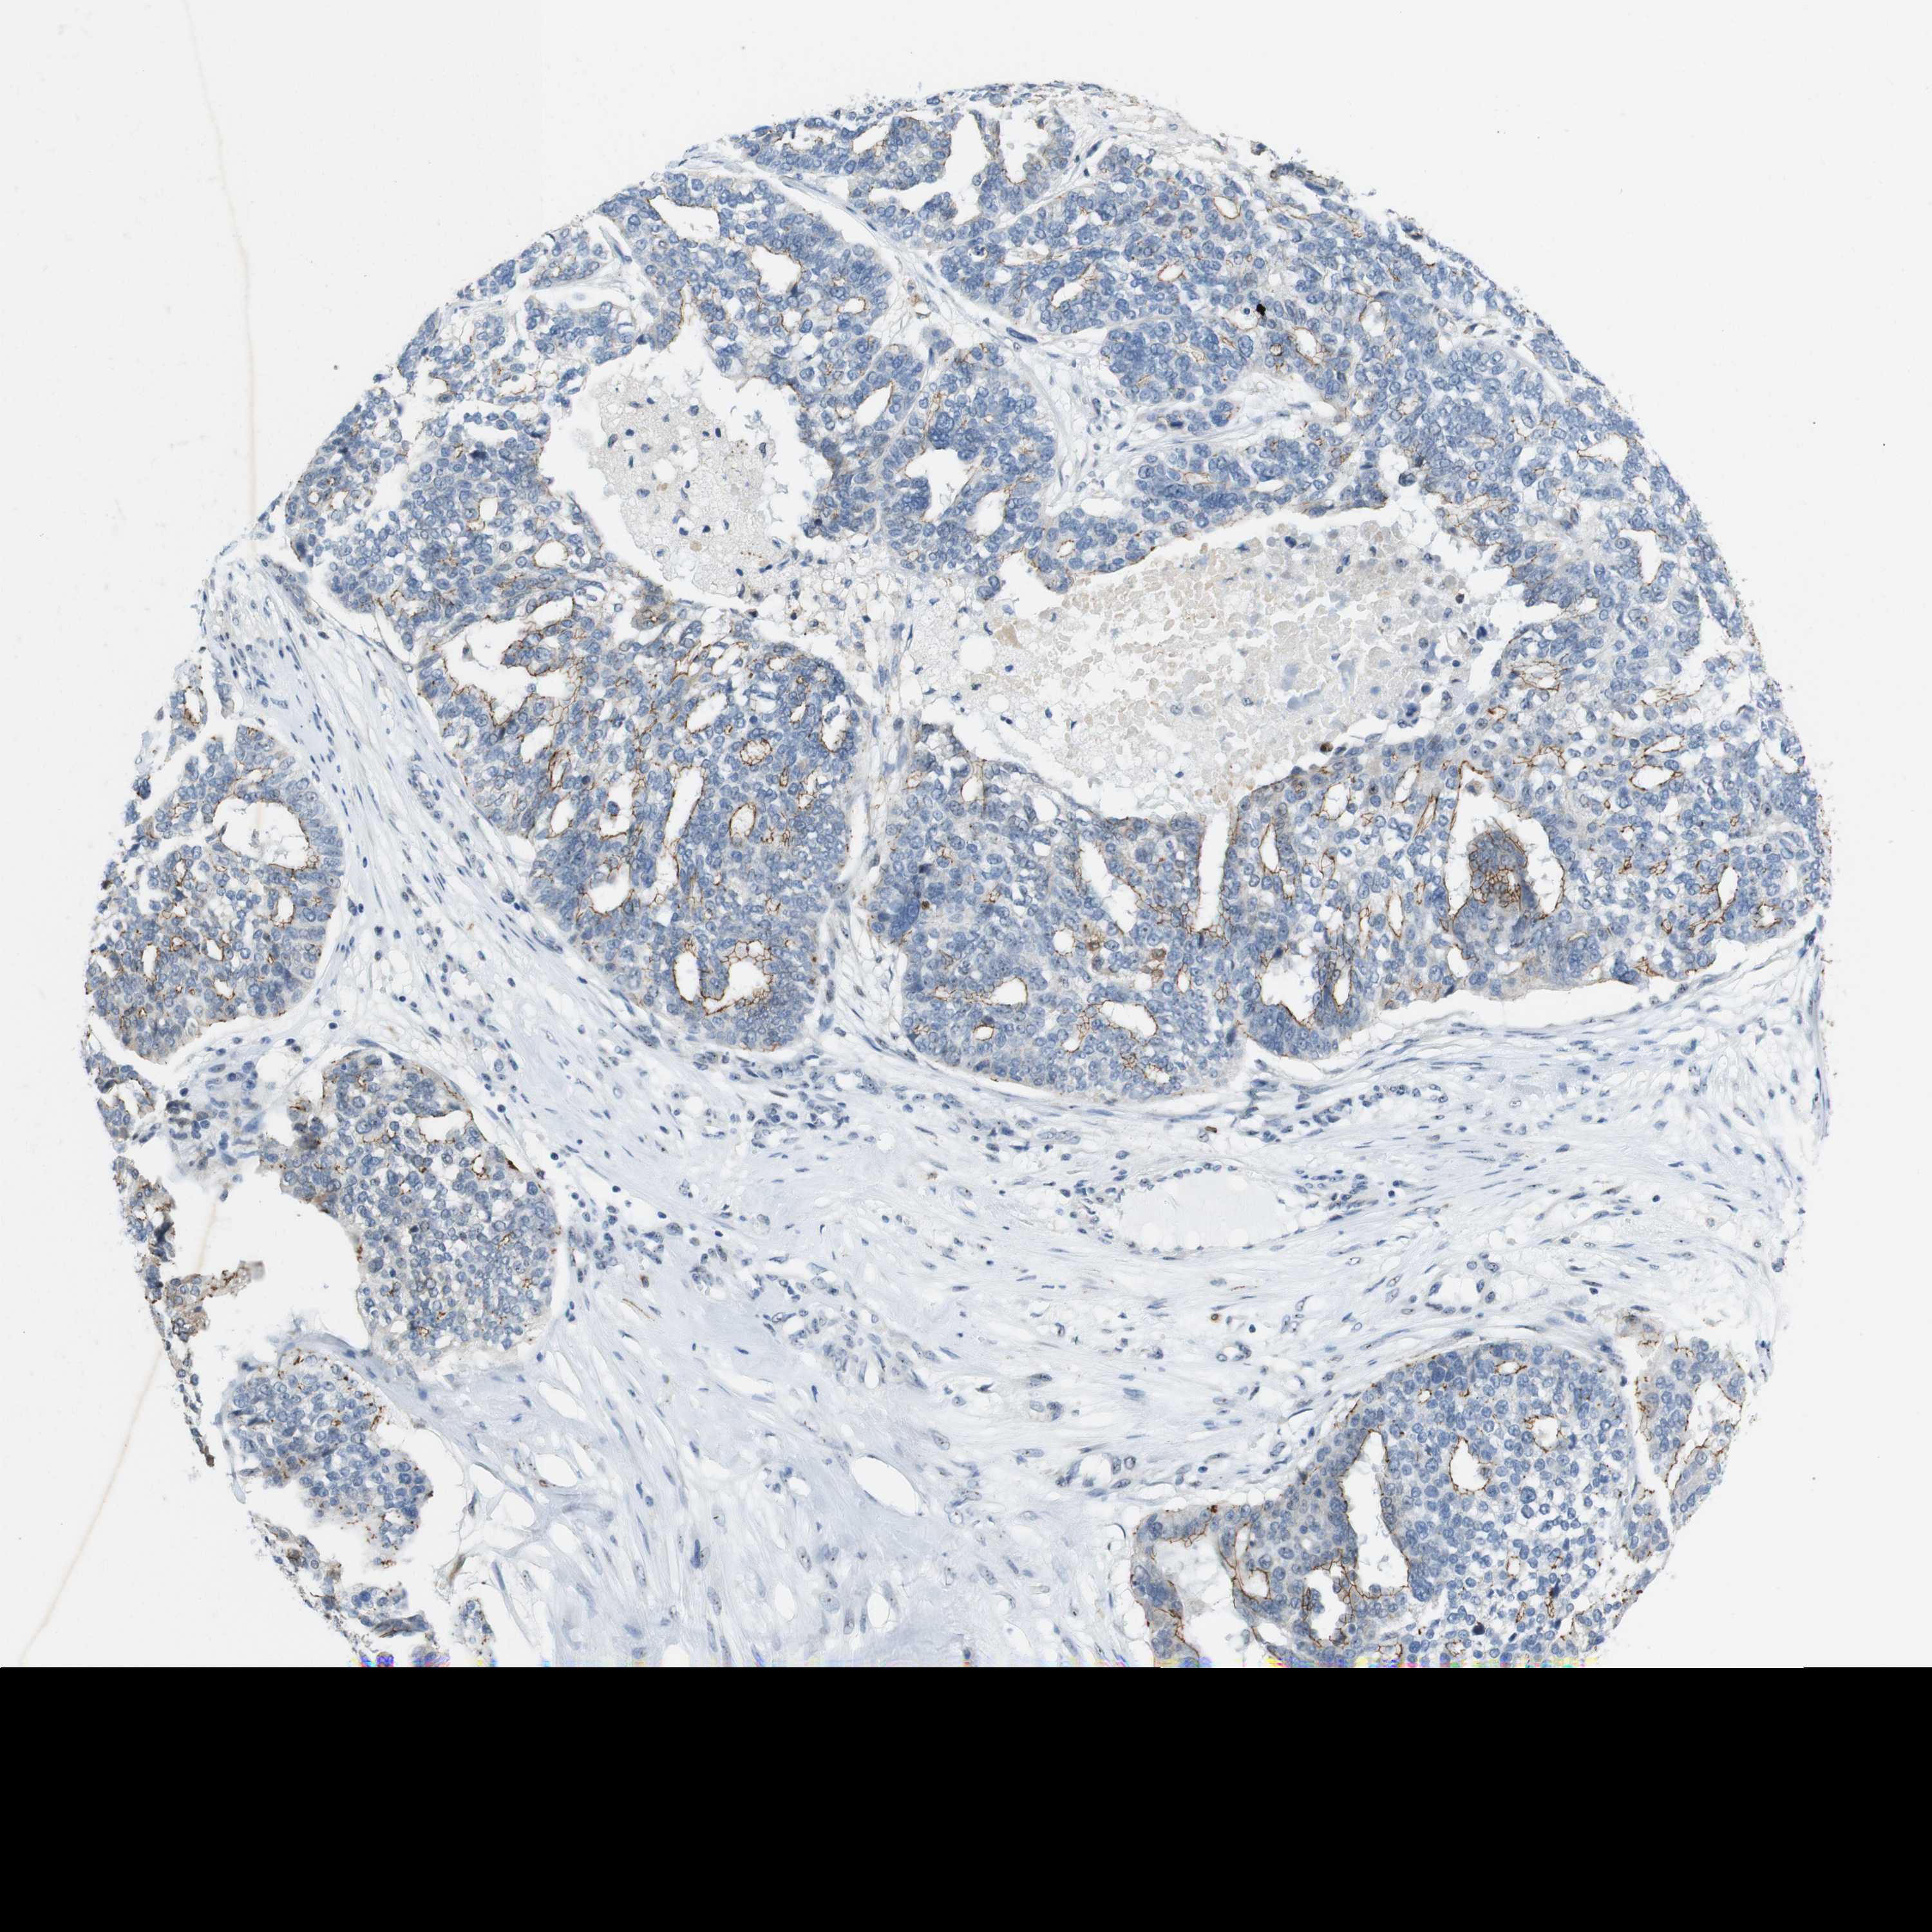

OVARIAN CANCER - Protein expressioni

A mouse-over function shows sample information and annotation data. Click on an image to view it in a full screen mode. Samples can be filtered based on level of antibody staining by selecting one or several of the following categories: high, medium, low and not detected. The assay and annotation is described here.

Note that samples used for immunohistochemistry by the Human Protein Atlas do not correspond to samples in the TCGA dataset.

Antibody stainingi

Antibody staining in the annotated cell types in the current human tissue is reported as not detected, low, medium, or high, based on conventional immunohistochemistry profiling in selected tissues. This score is based on the combination of the staining intensity and fraction of stained cells.

Each image is clickable and will lead to virtual microscopy that enables deeper exploration of all samples and also displays staining intensity scores, fraction scores and subcellular localization as well as patient and tissue information for each sample.

Antibody HPA053337

Antibody CAB013244

Cystadenocarcinoma, serous, NOS

Cystadenocarcinoma, mucinous, NOS

Carcinoma, endometroid